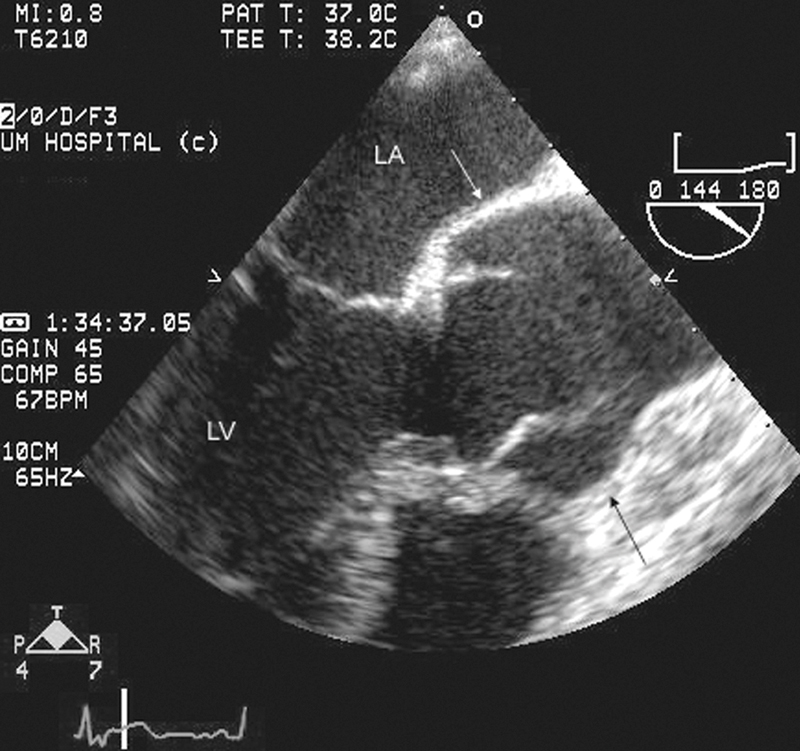

فحوصات تشخيصية لبعض امراض القلب والشرايين التاجية